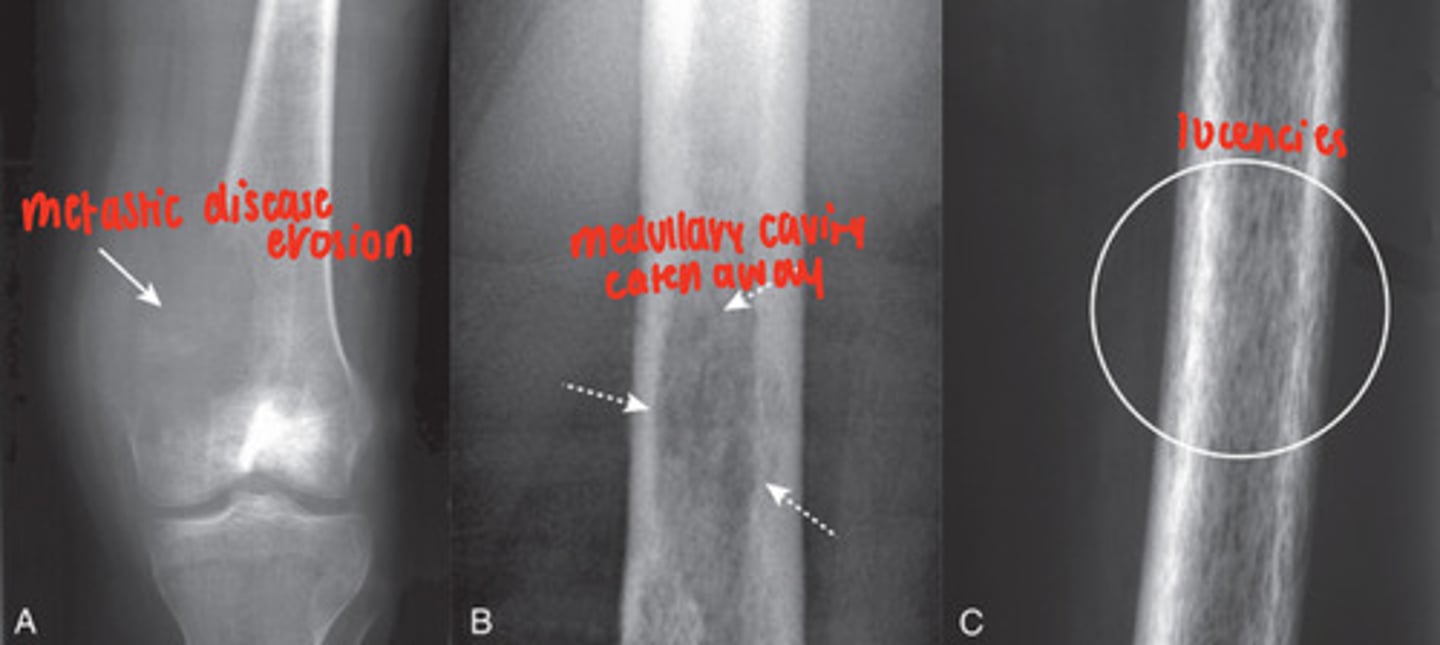

osteolytic metastatic disease

malignancy spread causes bone destruction, mainly medullary cavity but cortex can be involved

MRI- excellent at demonstrating status of the medullary cavity

- irregularly shaped, lucent bone lesions

pedicle sign

osteolytic metastatic disease destroys pedicles because of their blood supply